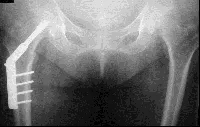

• Les fractures de la région trochantérienne sont le plus souvent stabilisées par ostéosynthèse (pose de vis et de plaques ou d’une vis solidaire d’un clou) mais peuvent être aussi traitées, plus rarement, par une prothèse, dans certains cas.

Image

vis plaque

Vis-plaque